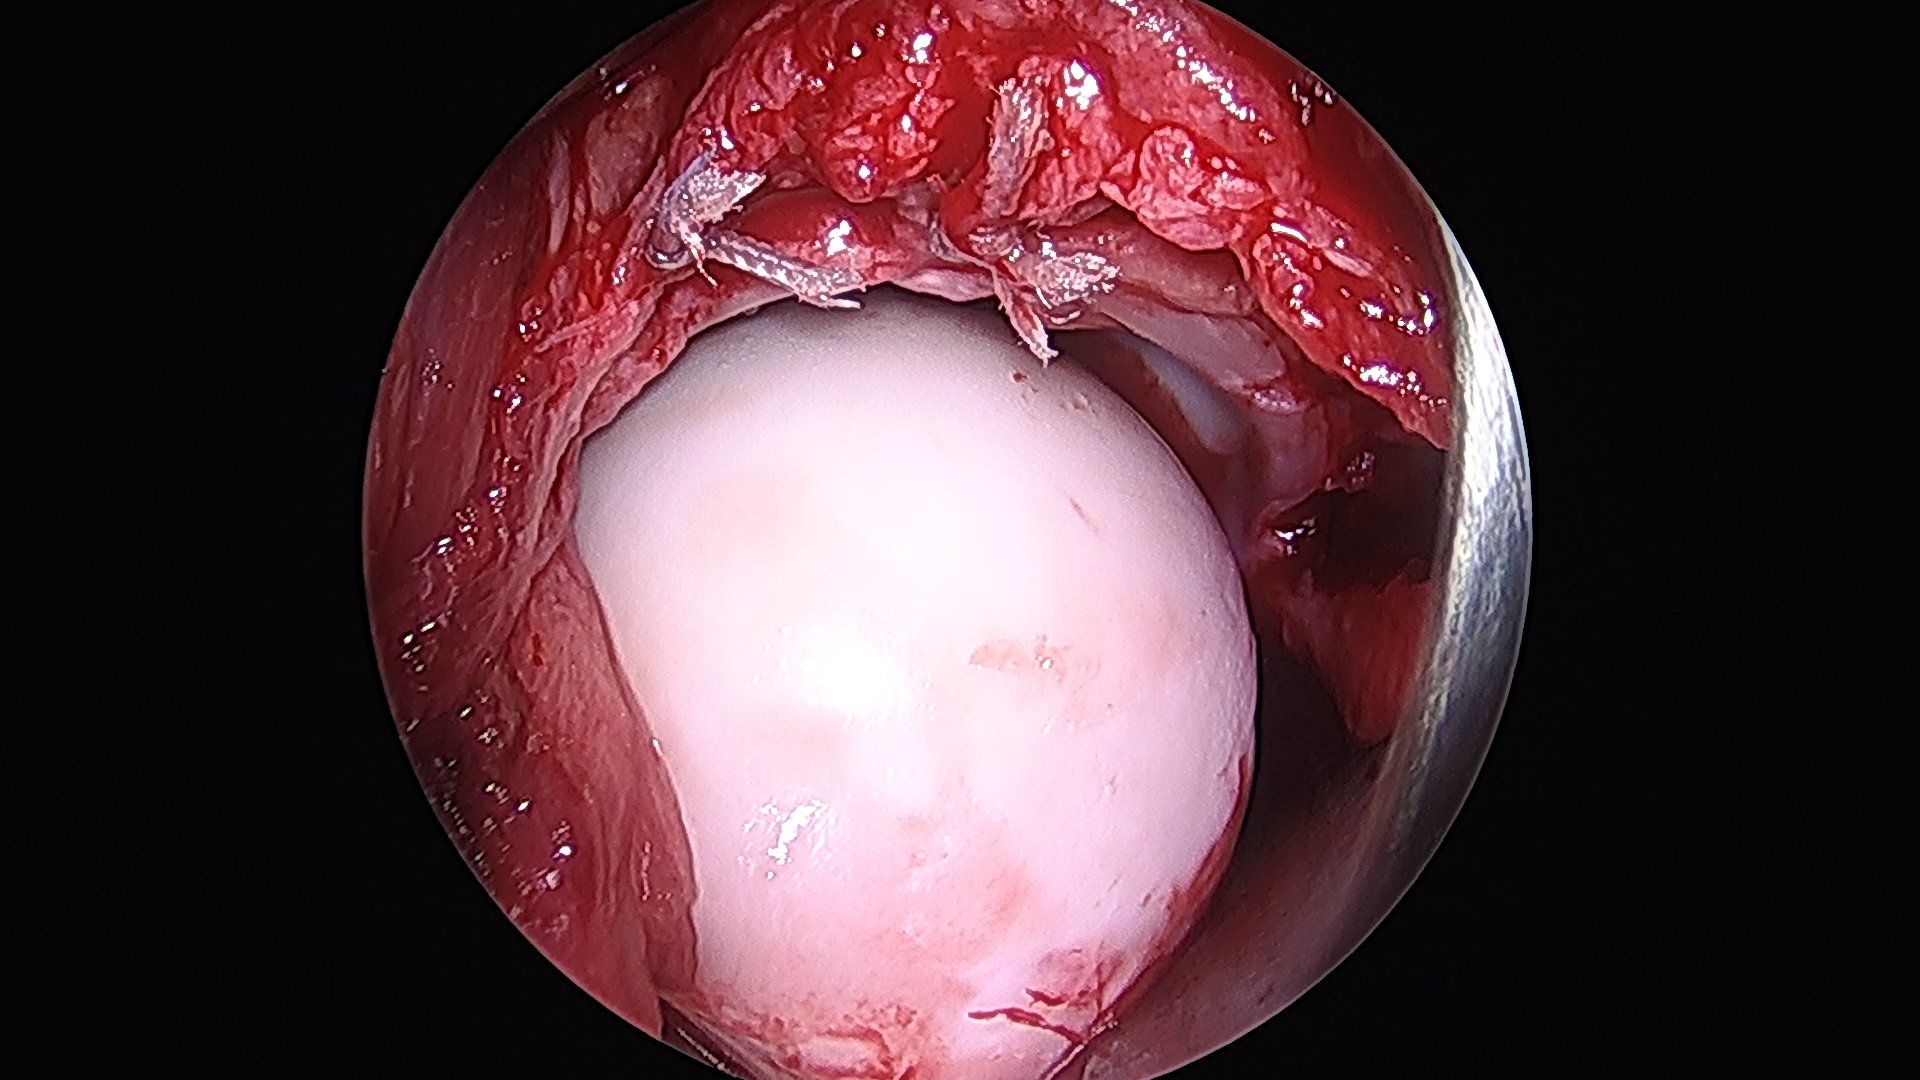

Details of the following steps have been described by (Hartmann and Gunther 2009). By disconnecting the traction device, a dynamic evaluation of hip motion under direct observation of labrum, head and neck is performed and the area of reshaping of the head–neck junction can be clearly defined (fig. 3d).

Visualisation of the central compartment of the joint for chondral and labral lesions is performed arthroscopically. After having applied distraction of the leg a 3.5 mm arthroscope (70° optics) is inserted from the anterior incision. Fluid management as in normal arthroscopy with continuous flow allows proper visualisation. The anterosuperior and lateral parts of the acetabular labrum with the adjacent articular cartilage and the femoral head are inspected. These are the areas where most of the relevant labrum and cartilage lesions are located. Depending on the amount as well as type of damage, reconstructive procedures are performed with and without traction. Ossified or ruptured parts of the labrum are resected or refixation of a partially detached labrum is performed with resorbable suture anchors (fig. 4a and 4b). Refixation of debonded cartilage flaps (fig. 5 a–d) curettage and microfracturing of damaged cartilage fragments and even autologous chondrocyte transplantation is possible (Bretschneider et al. 2020).

Contouring of the femoral head and neck by osteochondroplasty is performed with a partially covered acromionizer (fig. 6a and 6b).